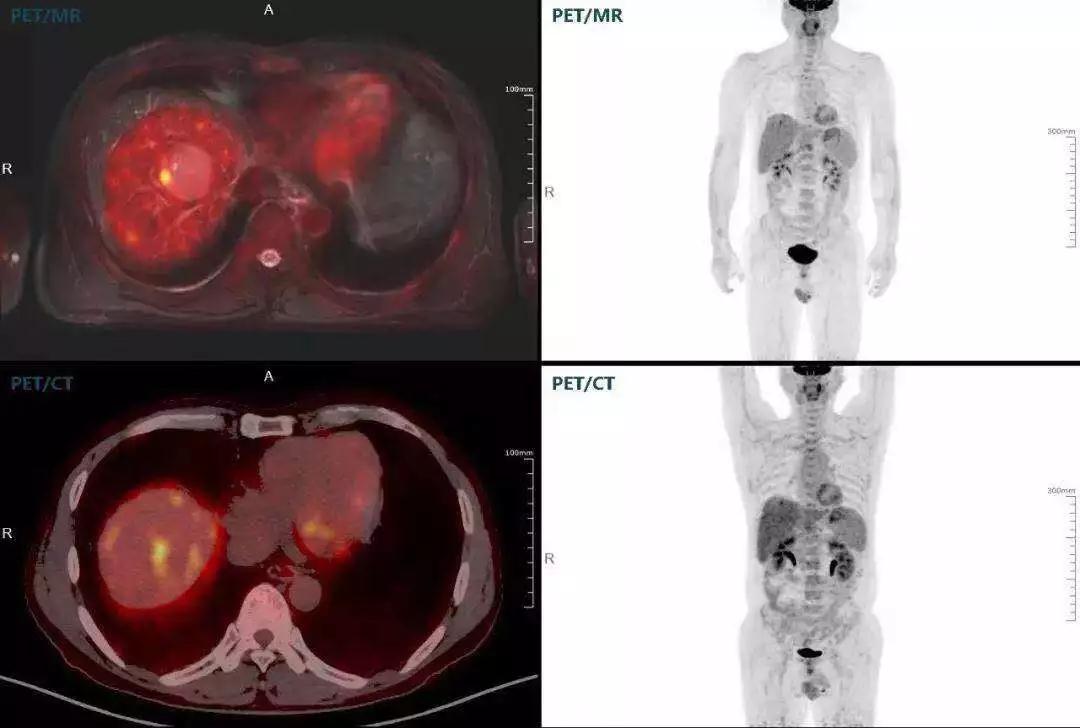

(對(duì)于同一例肝臟惡性腫瘤,PET-CT與PET/MR成像對(duì)比??梢钥吹?,聯(lián)影PET/MR圖像對(duì)腫瘤邊界和FDG高濃聚區(qū)域清晰顯示。)

中山醫(yī)院核醫(yī)學(xué)科在臨床實(shí)踐中發(fā)現(xiàn),基于聯(lián)影“時(shí)空一體”超清TOF PET/MR,不僅解剖信息和代謝信息能夠完美融合呈現(xiàn),同時(shí)精細(xì)展示局部病灶與周圍組織的復(fù)雜關(guān)系,并能全盤檢測(cè)病灶的全身轉(zhuǎn)移,為醫(yī)生臨床診斷提供更豐富信息。

中山醫(yī)院核醫(yī)學(xué)科基于聯(lián)影“時(shí)空一體”超清TOF PET/MR的融合顯像優(yōu)勢(shì),進(jìn)行了大量的臨床掃描,發(fā)現(xiàn)多例由MGUS向多發(fā)性骨髓瘤轉(zhuǎn)變,并從中總結(jié)出了一定的共同征象,未來可能實(shí)現(xiàn)多發(fā)性骨髓瘤的早期篩查。此外,PET/MR在多發(fā)性骨髓瘤的療效評(píng)估方面,也存在顯著優(yōu)勢(shì)。

(男性,53歲。確診多發(fā)性骨髓瘤10月。經(jīng)過7周期VCD方案化療后,現(xiàn)行療效評(píng)價(jià)。)